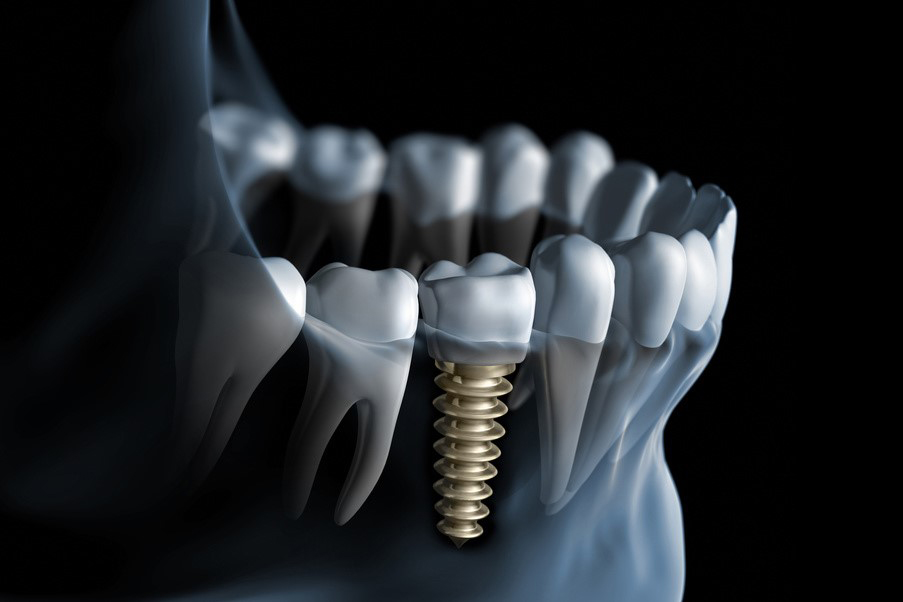

Tapahtuu nykyään miltei poikkeuksetta hammasimplantilla eli keinojuurella sekä sen päälle kiinni ruuvattavalla näkyvällä osalla eli impanttikruunulla. Useita vierekkäisiä puuttuvia hampaita korvatessa käytetään usean implantin varaan kiinnitettäviä implanttisitoja.

Implanttikokonaisuus koostuu luuhun ruuvattavasta implantista eli fikstuurasta, näkyvästä osasta eli implanttikruunusta ja näitä yhdistävästä implanttijatkeesta jonka avulla kruunu kiinnittyy ruuviin.